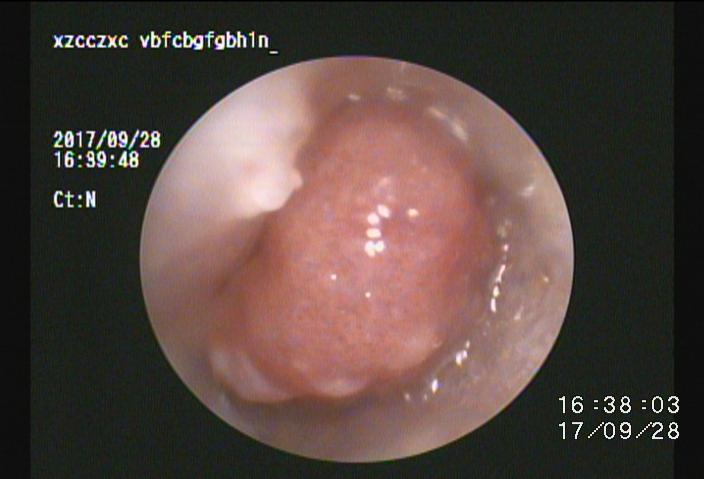

・耳垢や毛、ポリープや異物などを除去することで本来の環境に近づける